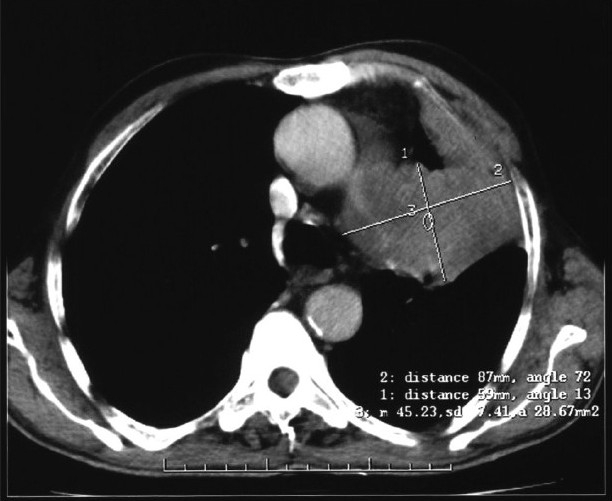

A 70-year-old man presented with a complaint of swelling and pain in the right ring finger. The swelling gradually increased in size and became painful over a one-month period. He had no other complaints. Physical examination revealed no clinical findings other than swelling in the right ring finger proximally. The swelling was of mixed consistency, tender to palpation, and it restricted finger movement. A radiograph of the right hand showed an osteolytic lesion in the proximal phalanx of the ring finger [Figure 1]. FNAC of the swelling suggested metastatic adenocarcinoma. The hematological and biochemical profiles were normal. Ultrasonography of the whole abdomen and the skeletal survey was within normal limits [Figure 2]. A plain chest radiograph showed a mass lesion in the midzone of the right lung [Figure 3]. Bronchoscopic biopsy and aspiration cytology revealed adenocarcinoma of the lung. A bone scan showed increased uptake in the proximal phalanx of the right ring finger. We planned systemic chemotherapy and palliative radiotherapy to the finger with a nonsteroidal analgesic for relieving pain.

| Figure 2 Chest CT scan showing left mid lobe mass

Bone metastasis in distal parts of the extremities is very rare.[9–11] The first clinical description of peripheral bone metastases to the small bones of the hand was reported in a case of breast cancer, metastatic to the metacarpals, by Handley,[12] in 1960. The most common primary malignancy that metastasizes to the hand is lung carcinoma (42%) followed by the breast and kidney, each of which accounts for 11%.[5,12] The most common site of metastatic deposit to the hand is the distal phalanx. The incidence of metastasis in hand bones is 17% in metacarpals, 66% in phalanges, and 17% in carpal bones.[13] Bouvier et al. had described 256 cases of peripheral bone metastases in 1971, however, the series includes the bones of the forearm and legs. Peripheral bone metastases are mostly associated with disseminated disease, but sometimes account for the first symptom of the neoplasm. Patients may first receive medical attention as the result of skeletal metastasis from an unknown primary tumor. Imaging studies in such individuals may help to identify the primary lesion. A chest CT scan may occasionally be helpful in diagnosing lung cancer, which is not obvious on a plain chest radiograph. Therefore, a chest CT scan and bronchoscopy are undertaken when there is a clinical indication. In a reported case, at the time of initial diagnosis the right hand ring finger lesion was recognized as a primary bone tumor in a radiograph, because of the unusual localization of the bone metastasis. Among lung cancers, adenocarcinomas are more heterogeneous in progression than other cell types of lung cancer. In patients with advanced lung cancer, the major goal of treatment is recovery of the performance status of the patient and relief from pain. In a certain percent of cases, however, intensive systemic chemotherapy would be indicated as an adjuvant to local therapy such as radiotherapy and / or surgical procedures. Radiotherapy of 800 cGy single fraction at the metastatic bone site and oral analgesics improved the quality of life in our patient.